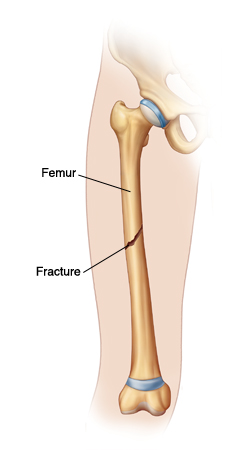

When Your Child Has a Femur Fracture

Your child has a break (fracture) in their thighbone (femur). The femur is a strong bone and is very hard to break. So a femur fracture is often the result of great force during severe trauma (such as a car accident, bad fall, or serious sports injury). Your child may have already been seen in an emergency room for initial treatment for the fracture. But more treatment is needed to help the leg heal. A child with a femur fracture is likely to be referred to a surgeon specializing in bone and joint problems (orthopedic surgeon).

Types of fractures

A bone can break in many ways. Here are some fracture types you may hear about:

Displaced fracture. The broken bone ends don't line up.

Nondisplaced fracture.The broken ends are lined up.

Open fracture.The bone shows through the skin. These used to be called compound fractures.

Closed fracture. There is no break in the skin.

Comminuted fracture. The bone is broken into more than two pieces.